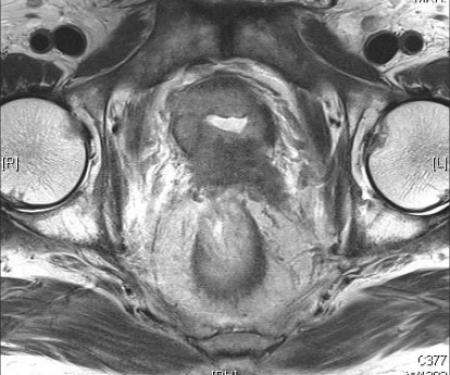

Prostate Cancer